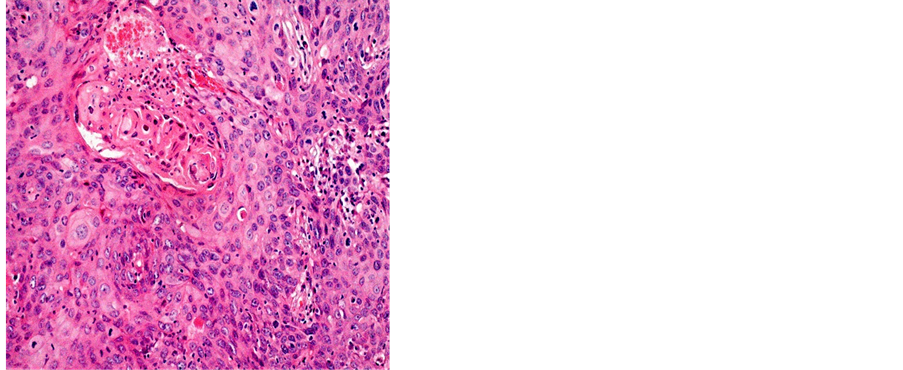

Table 2 shows the distribution of histological types of cancers diagnosed during the study. A total of 1687 (81.18%) cases of squamous cell carcinoma (SCC) and 269 (12.95%) cases of adenocarcinoma (ADK) have been identified (Figures 3-5).

Figure 3. Well differentiated SCC (a) 400×; (b) 200×.